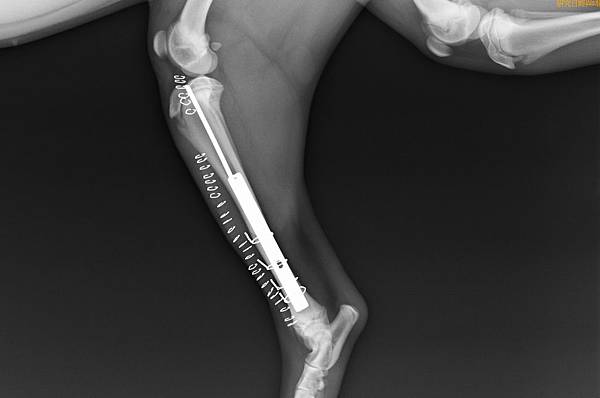

上圖為手術後X光

3.jpg

4.jpg

手術兩周就可以正常行走